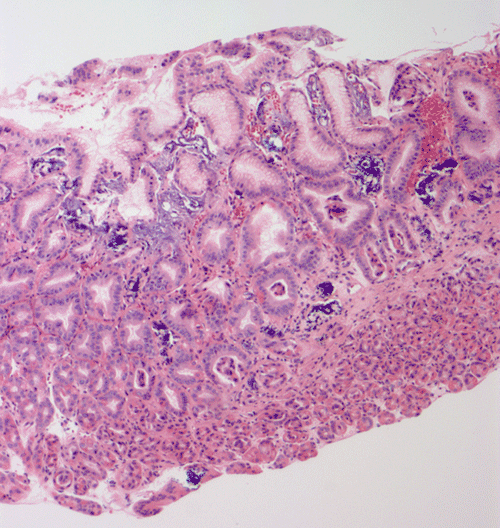

Pathology of the case: At low power magnification, the biopsy appears to be a portion of gastric fundic-type mucosa (Panel A).  Prominent scattered irregular, amorphous basophilic substances are present in small deposits in the superficial lamina propria, abutting the gastric epithelium (Panel A, B, and C).  The mucosa has a reactive appearance, with enlarged nuclei, prominent nucleoli and regenerative appearing glands (best seen in Panel C).  An iron stain is negative on these deposits arguing against that these are iron containing substances, hemosiderin or other hemoglobin breakdown products (Panel D).  These irregular, basophilic, amorphous material is positive by von Kossa stain (Panels E), consistent with calcium depositions.  There is no evidence of intestinal metaplasia, dysplasia, or neoplasia.  No significant foveolar hyperplasia or inflammation is present.